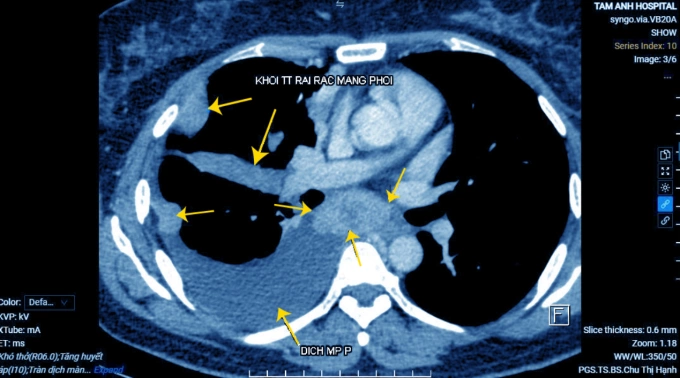

Các khối tổn thương màng phổi dày đặc trên phim chụp CT. Ảnh: Bệnh viện Đa khoa Tâm Anh

Bà Phương khó thở kèm đau tức ngực phải, ho khan kéo dài một tháng. Khám ở Canada ghi nhận bất thường nhưng qua nhiều tháng bà chưa đặt được lịch để bác sĩ chẩn đoán chuyên sâu, về Việt Nam đến Bệnh viện Đa khoa Tâm Anh Hà Nội khám. Kết quả chụp cắt lớp vi tính cho thấy tổn thương kích thước 3 cm ở thùy dưới phổi phải, xẹp thùy dưới phổi, tràn dịch màng phổi phải.